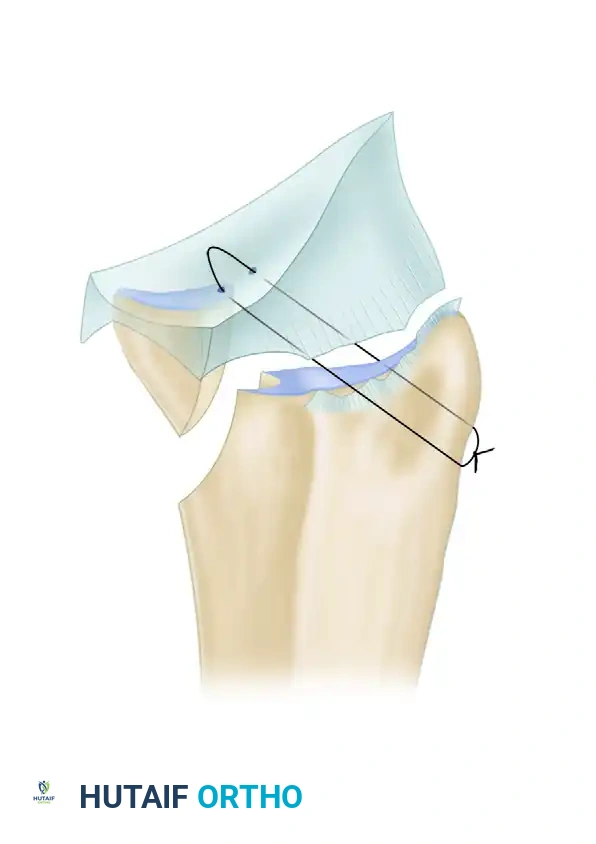

3. Proximal Row Carpectomy (PRC)

A proximal row carpectomy is typically incorporated with the fusion in these severe cases.

* Rationale: Excising the proximal carpal row (scaphoid, lunate, and triquetrum) effectively shortens the skeletal column of the wrist. This skeletal shortening is paramount; it allows the severe flexion contracture to be corrected without placing catastrophic stretch on the median nerve or requiring massive, morbid flexor tendon lengthenings.

* Execution: Use a combination of sharp dissection, elevators, and rongeurs to excise the proximal row. Take care to protect the volar radiocarpal ligaments to maintain a soft tissue hinge.